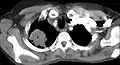

CT scan showing a Pancoast tumor (labeled as P, non-small cell lung carcinoma, left lung), from a 47-year-old female smoker